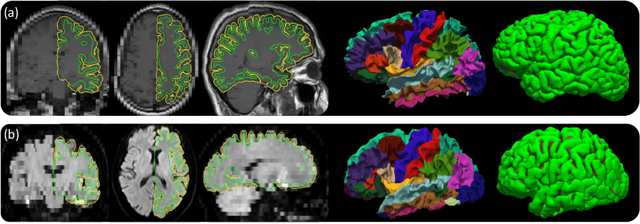

Abstract:Surface-based cortical analysis is valuable for a variety of neuroimaging tasks, such as spatial normalization, parcellation, and gray matter (GM) thickness estimation. However, most tools for estimating cortical surfaces work exclusively on scans with at least 1 mm isotropic resolution and are tuned to a specific magnetic resonance (MR) contrast, often T1-weighted (T1w). This precludes application using most clinical MR scans, which are very heterogeneous in terms of contrast and resolution. Here, we use synthetic domain-randomized data to train the first neural network for explicit estimation of cortical surfaces from scans of any contrast and resolution, without retraining. Our method deforms a template mesh to the white matter (WM) surface, which guarantees topological correctness. This mesh is further deformed to estimate the GM surface. We compare our method to recon-all-clinical (RAC), an implicit surface reconstruction method which is currently the only other tool capable of processing heterogeneous clinical MR scans, on ADNI and a large clinical dataset (n=1,332). We show a approximately 50 % reduction in cortical thickness error (from 0.50 to 0.24 mm) with respect to RAC and better recovery of the aging-related cortical thinning patterns detected by FreeSurfer on high-resolution T1w scans. Our method enables fast and accurate surface reconstruction of clinical scans, allowing studies (1) with sample sizes far beyond what is feasible in a research setting, and (2) of clinical populations that are difficult to enroll in research studies. The code is publicly available at https://github.com/simnibs/brainnet.

Abstract:Surface-based analysis of the cerebral cortex is ubiquitous in human neuroimaging with MRI. It is crucial for cortical registration, parcellation, and thickness estimation. Traditionally, these analyses require high-resolution, isotropic scans with good gray-white matter contrast, typically a 1mm T1-weighted scan. This excludes most clinical MRI scans, which are often anisotropic and lack the necessary T1 contrast. To enable large-scale neuroimaging studies using vast clinical data, we introduce recon-all-clinical, a novel method for cortical reconstruction, registration, parcellation, and thickness estimation in brain MRI scans of any resolution and contrast. Our approach employs a hybrid analysis method that combines a convolutional neural network (CNN) trained with domain randomization to predict signed distance functions (SDFs) and classical geometry processing for accurate surface placement while maintaining topological and geometric constraints. The method does not require retraining for different acquisitions, thus simplifying the analysis of heterogeneous clinical datasets. We tested recon-all-clinical on multiple datasets, including over 19,000 clinical scans. The method consistently produced precise cortical reconstructions and high parcellation accuracy across varied MRI contrasts and resolutions. Cortical thickness estimates are precise enough to capture aging effects independently of MRI contrast, although accuracy varies with slice thickness. Our method is publicly available at https://surfer.nmr.mgh.harvard.edu/fswiki/recon-all-clinical, enabling researchers to perform detailed cortical analysis on the huge amounts of already existing clinical MRI scans. This advancement may be particularly valuable for studying rare diseases and underrepresented populations where research-grade MRI data is scarce.

Abstract:Surface analysis of the cortex is ubiquitous in human neuroimaging with MRI, e.g., for cortical registration, parcellation, or thickness estimation. The convoluted cortical geometry requires isotropic scans (e.g., 1mm MPRAGEs) and good gray-white matter contrast for 3D reconstruction. This precludes the analysis of most brain MRI scans acquired for clinical purposes. Analyzing such scans would enable neuroimaging studies with sample sizes that cannot be achieved with current research datasets, particularly for underrepresented populations and rare diseases. Here we present the first method for cortical reconstruction, registration, parcellation, and thickness estimation for clinical brain MRI scans of any resolution and pulse sequence. The methods has a learning component and a classical optimization module. The former uses domain randomization to train a CNN that predicts an implicit representation of the white matter and pial surfaces (a signed distance function) at 1mm isotropic resolution, independently of the pulse sequence and resolution of the input. The latter uses geometry processing to place the surfaces while accurately satisfying topological and geometric constraints, thus enabling subsequent parcellation and thickness estimation with existing methods. We present results on 5mm axial FLAIR scans from ADNI and on a highly heterogeneous clinical dataset with 5,000 scans. Code and data are publicly available at https://surfer.nmr.mgh.harvard.edu/fswiki/recon-all-clinical